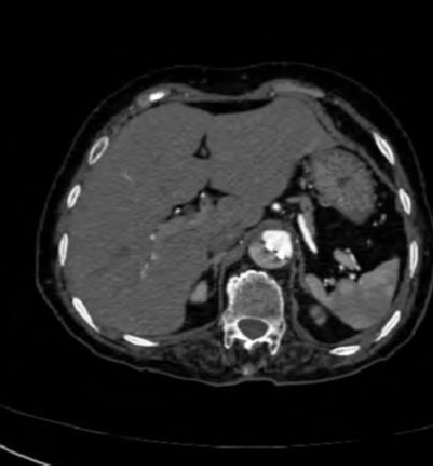

病例3

下图的胸部CT平扫,有什么致命的问题?

图7

仔细一看,主动脉里面有线样阴影!并且,线样阴影两边的密度一高一低!

图8

增强CT一看,主动脉夹层,密度相对高的是流动的血液!

图9